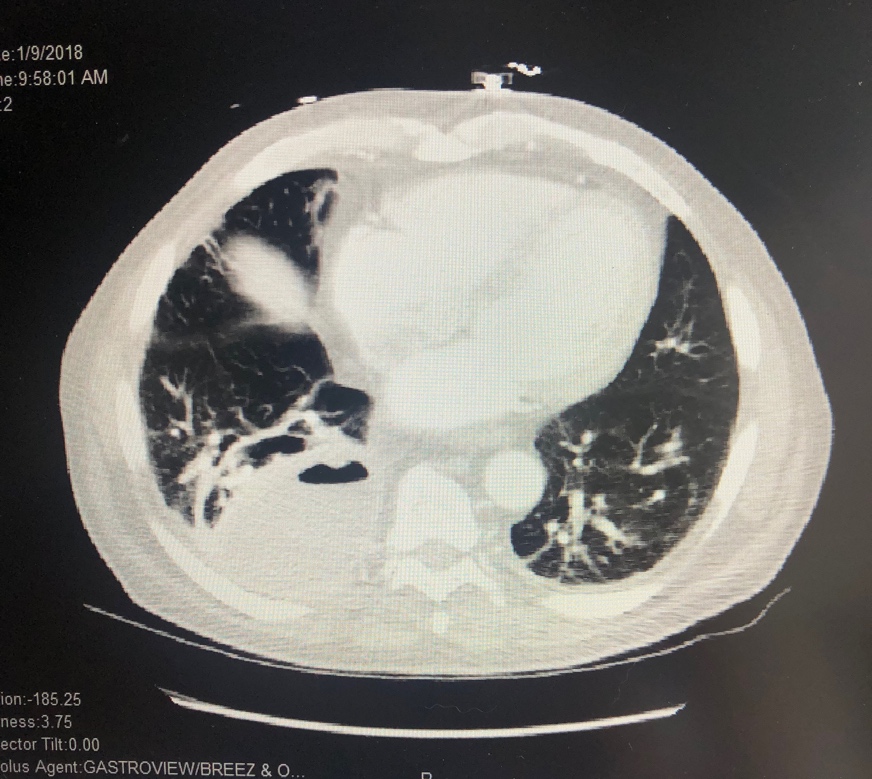

Chest radiography showed a new right lower lung mass. A chest computed tomography (CT) scan with contrast revealed a 3.7-cm cavitary lesion in the left upper lobe of the lung and an 8.3-cm necrotic-appearing cavitary lesion in the right lower lobe (Figure 1).

Figure 1. CT scan with contrast showing a right lower lung abscess.